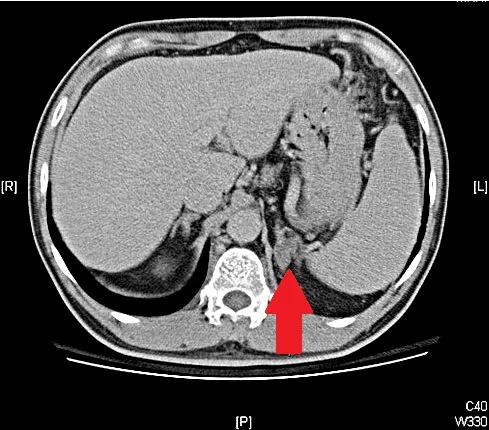

經電腦斷層發現,病患左側腎上腺出現腫瘤 (紅色箭頭處)。院方提供

黃民評醫師診斷林先生是心臟衰竭,但因他年紀輕輕就有高血壓,研判「可能有其他問題」,進一步安排抽血結果有低血鉀情形,接著進行電腦斷層檢查,竟然在腎上腺發現一顆腫瘤,這是由腎上腺分泌的荷爾蒙所形成的腫瘤,除了會造成高血壓影響心臟功能之外,還會干擾體內代謝導致胰島素的阻抗變強,因此讓林先生的血糖變得難以控制,心臟長期以來經歷如此折磨就變成了心臟衰竭,幸好在切除腫瘤後,血壓、血糖以及心臟衰竭的控制已經大幅改善。